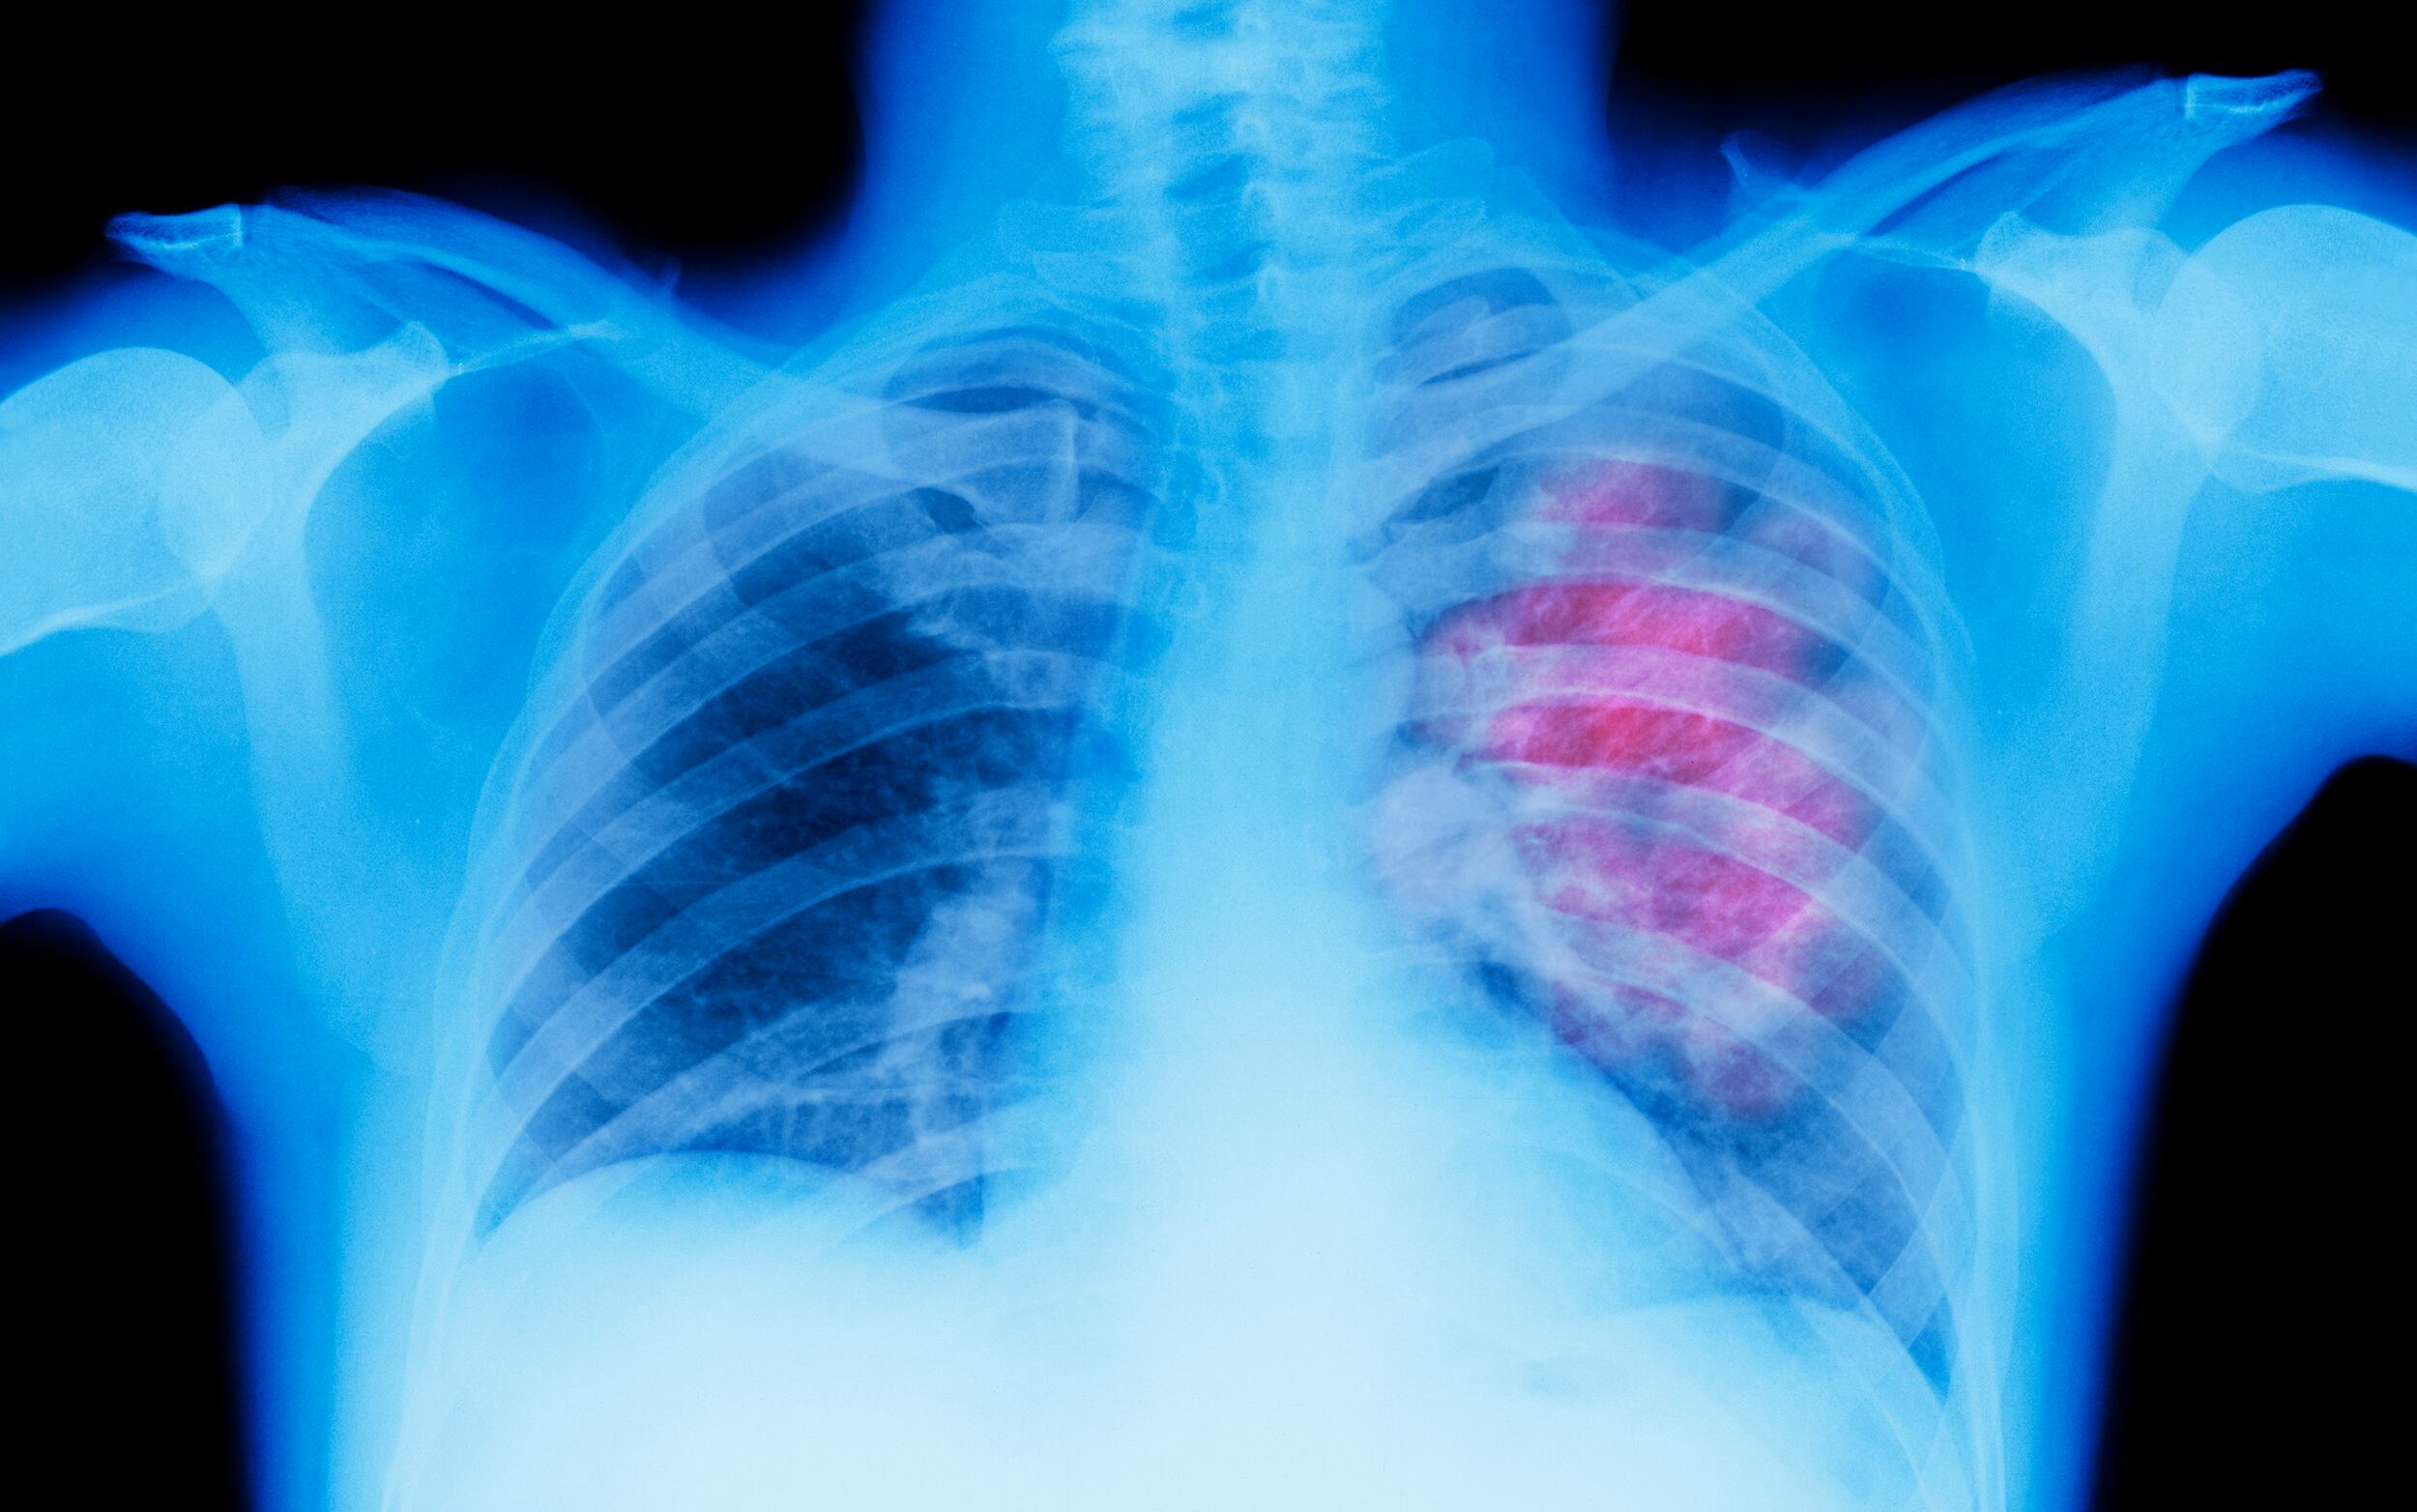

Los cánceres de pulmón, de estómago y de cuello uterino representaron casi la mitad de todos los casos de cáncer prevenibles a nivel mundial, con 1,8 millones, 784.073 y 662.044 diagnósticos atribuibles, respectivamente.

El cáncer de pulmón se relacionó principalmente con el tabaquismo y la contaminación del aire, mientras que el de estómago se atribuyó en gran medida a la infección por ‘Helicobacter pylori’ y el de cuello uterino al virus del papiloma humano (VPH).